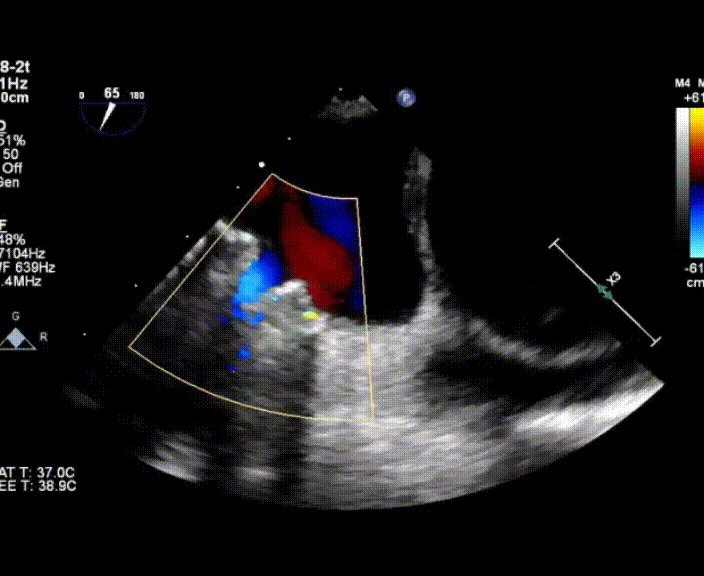

超聲心動圖提示:右心增大,右室肥厚,左室測值偏小,房間隔中份探及修補術后回聲,房水平未見殘余分流,三尖瓣重度反流,重度肺動脈高壓,中度肺動脈瓣反流,左室收縮功能測值正常,右室收縮功能減低 。

術中首先在局麻下穿刺股動脈、股靜脈,完成心導管檢查評估后轉為全麻,在食道超聲引導下穿刺房間隔,穿刺成功后將加硬導絲送入左上肺靜脈建立軌道,根據患者病情行球囊預擴張后植入6mm孔徑房間隔造孔支架,經透視及食道超聲評估支架左右盤展開良好,夾持于房間隔兩側,固定穩定、位置良好,食道彩超顯示房水平右向左為主分流,分流孔直徑符合預期大小,心導管檢查評估達到預期效果,釋放造孔支架。術后12h患者下床活動,恢復順利,擬于近日完善術后評估后出院。